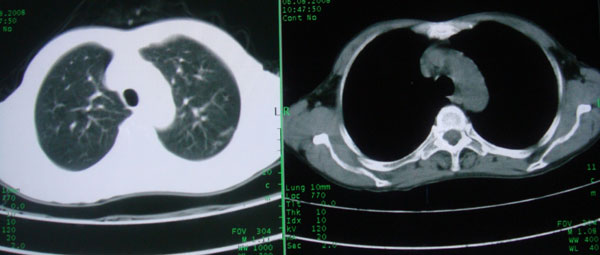

考虑支气管扩张并感染

1慢支伴感染;右下肺周围型肺癌。

1\\慢支并感染

2\\浸润型肺结核

本例应该是“慢性疾病并发多种合并症”即:慢支并感染并支气管扩张征!结合病灶分布 形态分析,不除外合并“继发性肺结核”!